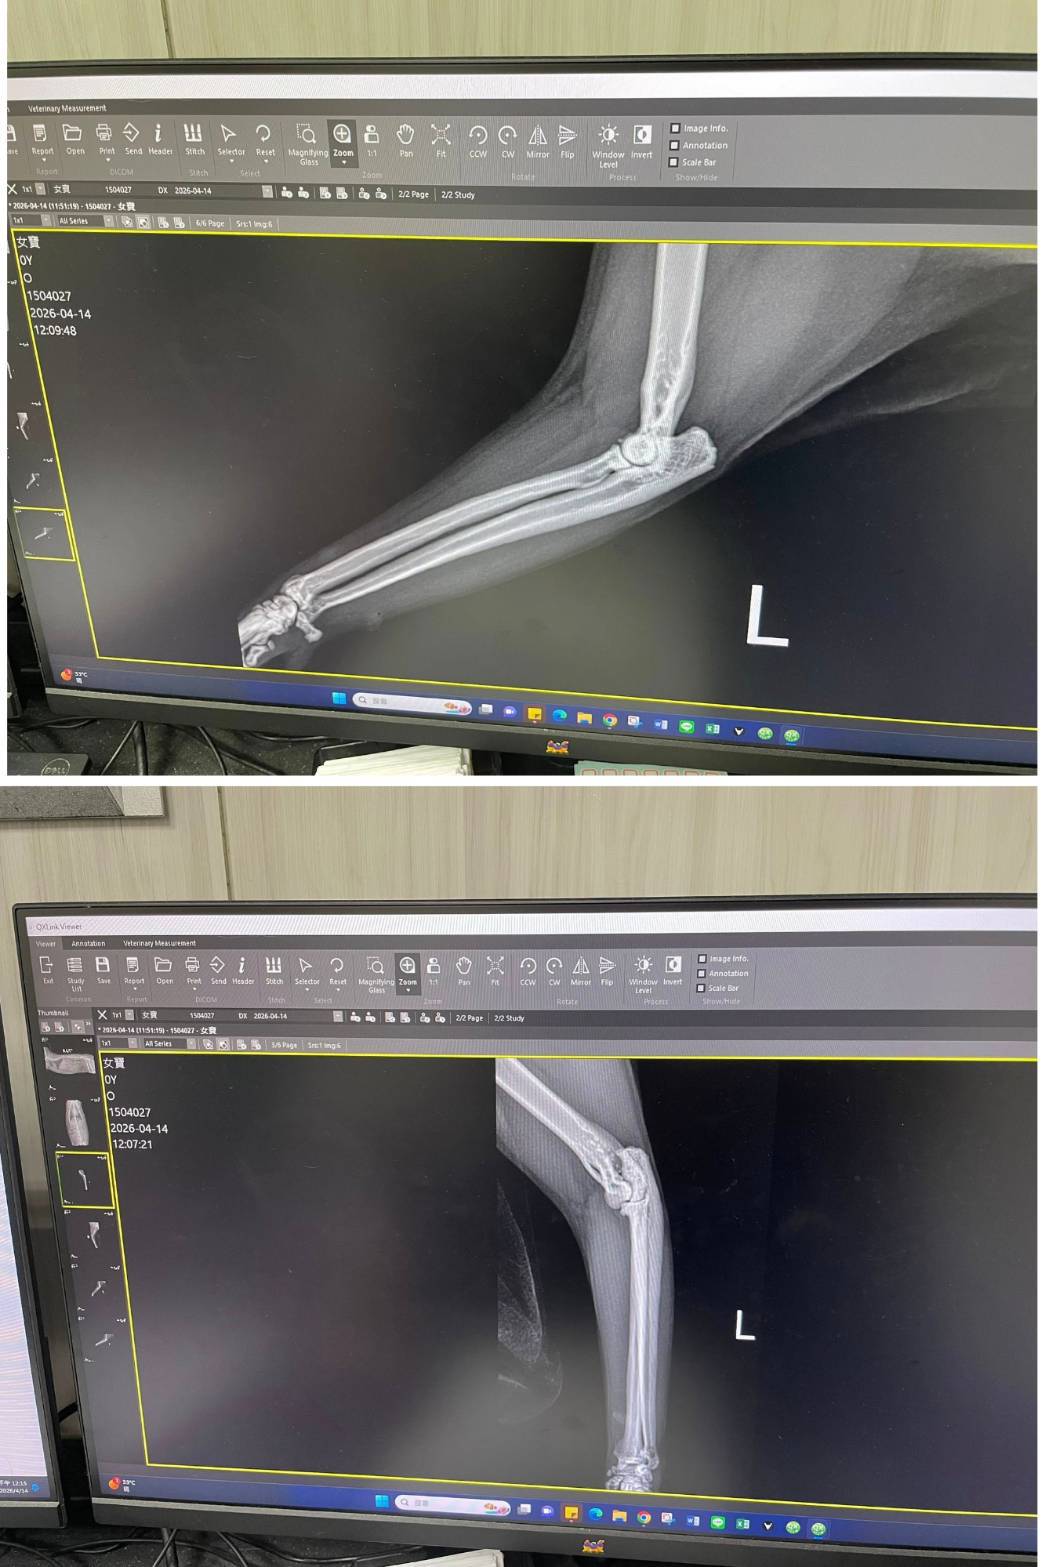

經X光檢查發現右前肢骨骼退化較嚴重,左邊也有一點骨骼退化;肺功能也是偏差;有牙周炎、牙齦萎縮所以齒根比較出來。X光有拍到兩顆東西,穿刺抹片檢查,淋巴細胞正常,淋巴結腫大。於醫院先點一錠除,並開立內用驅蟲藥,三個月後體外驅蟲需要再做一次。目前已於14日當日就醫後先行安置於協會幾日,因考量女寶年齡已大,汐止愛媽會帶回家中安置給女寶一個長久安穩的家。本筆醫助是女寶2026年4月14日於沐恩醫院看診的費用,包含血檢、X光、三合一、心臟快篩、皮膚抹片、一錠除滴劑及驅蟲藥。

右前肢比較嚴重左邊也有一點骨骼退化。

X光有拍到兩顆東西,穿刺抹片檢查,淋巴細胞正常,淋巴結腫大,